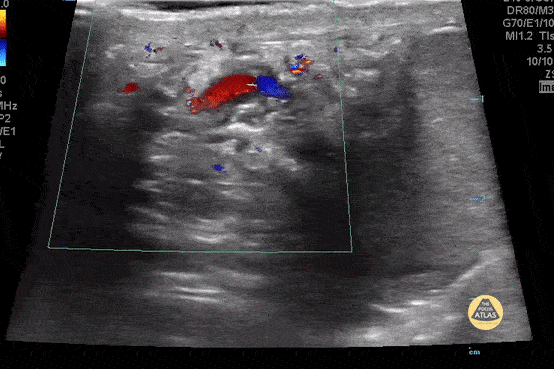

Normal spermatic cord. Flow should be linear as apposed to the "corkscrew" sign in torsion. Contributor: Paul Khalil, MD Nicklaus Children's Hospital @khalil3paul